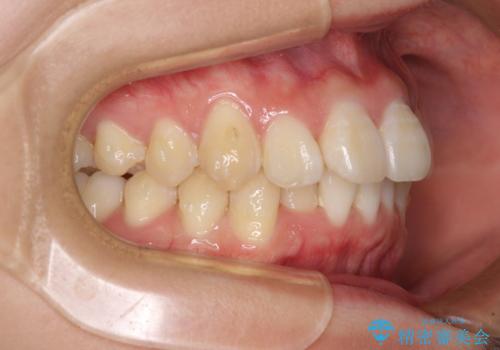

上下前歯の叢生をインビザラインできれいに

- 前歯のデコボコを気にして来院された患者様です。

前歯が重なっていることで口元が閉じにくくなっていたため、歯列全体の側方への拡大と、歯と歯の間を少し削ってスペースを獲得することとしました。